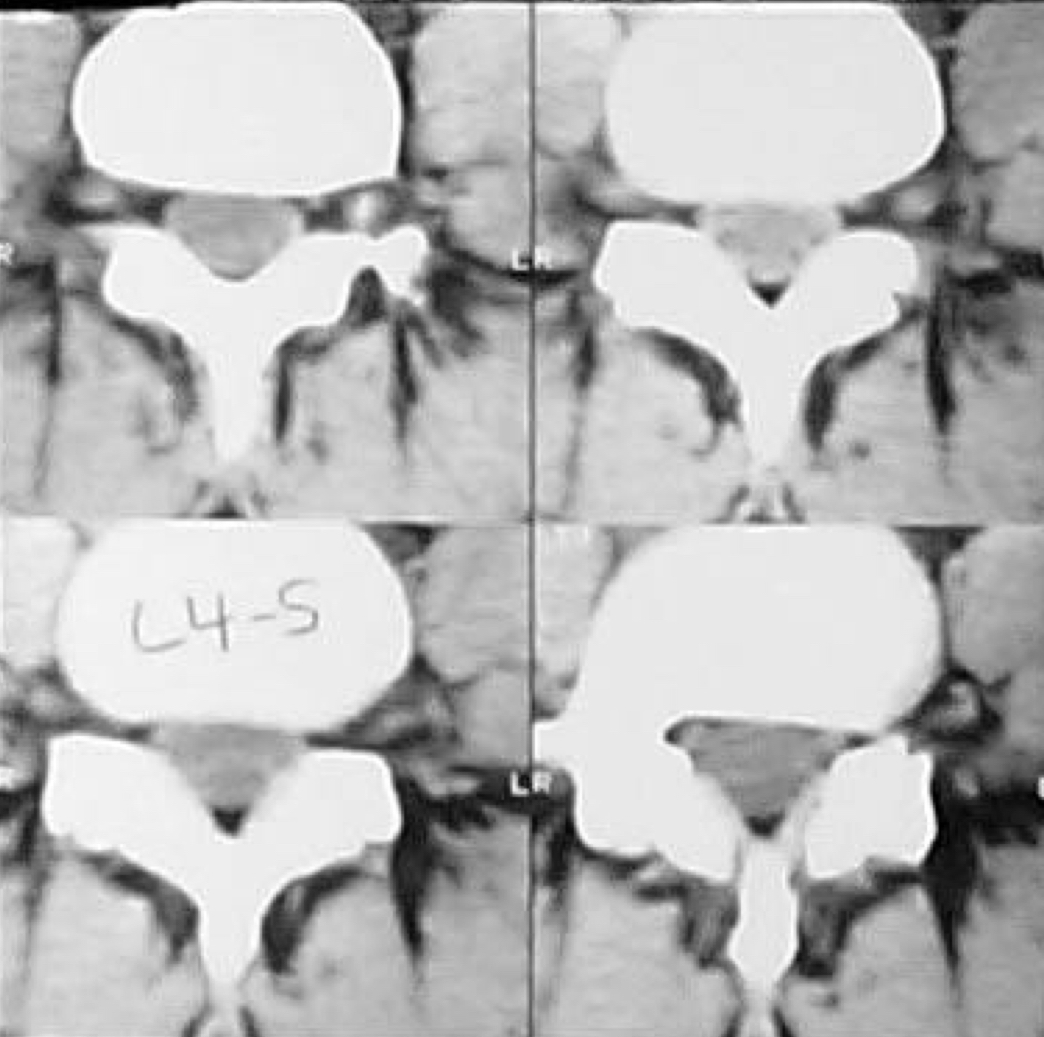

What kind of CT window is this? Why?

soft tissue window because soft tissue is opaque and more easily viewed